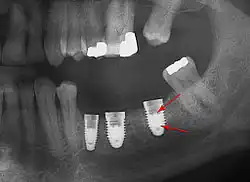

Beyond the possibility of mechanical failure[98] which may be due to poor prosthetic fitment, wear and tear, or user-induced actions such as bruxism, dental implants are also subject to peri-implant mucositis and peri-implantitis, where gum tissue and bone mass around the implant are resorbed, and the implant gradually becomes loose, and has to be removed.[99][100] In addition, although titanium is generally well tolerated by the body, there have been cases where the build-up of titanium particles released by the implant may cause systemic inflammatory response.[101] Because there is no dental enamel on an implant, it does not fail due to cavities like natural teeth. While large-scale, long-term studies are scarce, several systematic reviews estimate the long-term (five to ten years) survival of dental implants at 93–98 percent depending on their clinical use.[15][16][17] During initial development of implant retained teeth, all crowns were attached to the teeth with screws, but more recent advancements have allowed placement of crowns on the abutments with dental cement (akin to placing a crown on a tooth). This has created the potential for cement, that escapes from under the crown during cementation to get caught in the gingiva and create a peri-implantitis (see picture below). While the complication can occur, there does not appear to be any additional peri-implantitis in cement-retained crowns compared to screw-retained crowns overall.[102] In compound implants (two stage implants), between the actual implant and the superstructure (abutment) are gaps and cavities into which bacteria can penetrate from the oral cavity. Later these bacteria will return into the adjacent tissue and can cause periimplantitis.